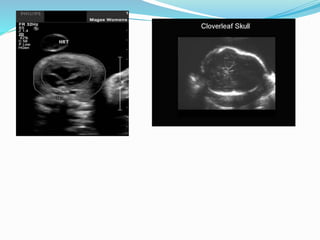

Thanatophoric Dysplasia

 Features:

 1- Short long bones well below the 3rd percentile

 2- Characteristic thickening of the metaphysis

 3-short splayed fingers (trident)

 4- Short ribs

 5- markedly small thorax

 6- Depressed nasal bridge + frontal bossing

Prognosis

 LETHAL

 Recurrence is low (dominant sporadic condition)